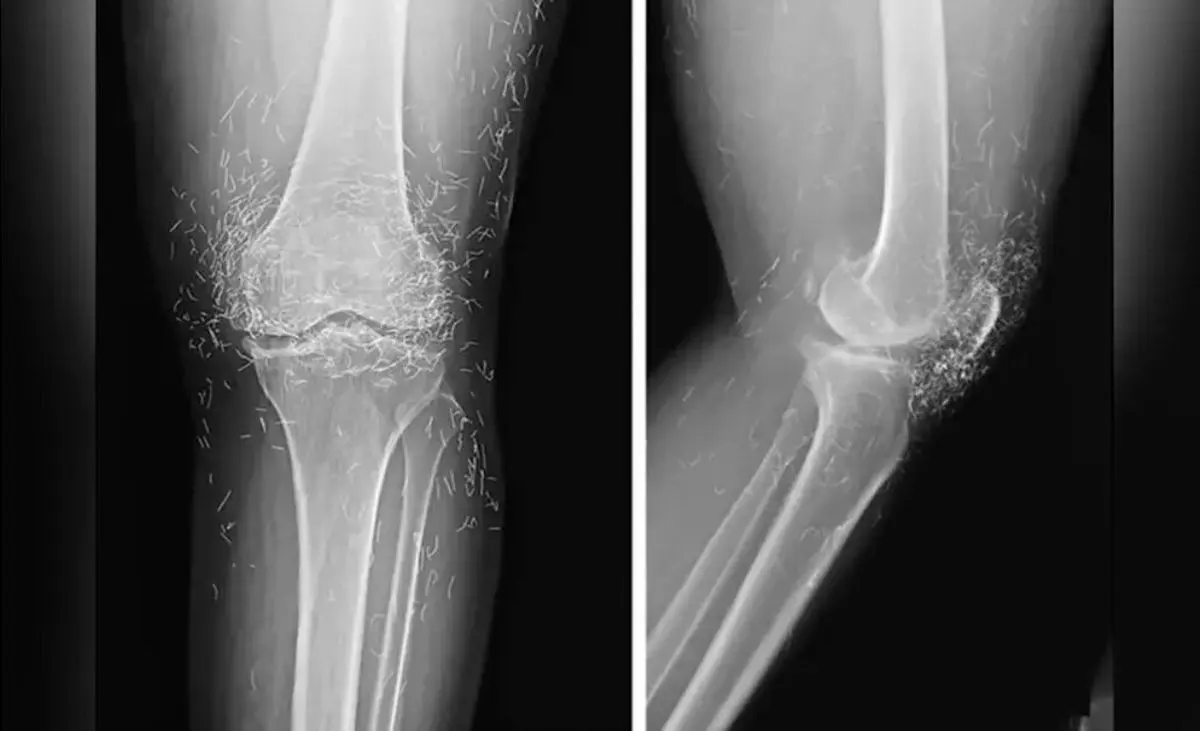

پزشکان کره جنوبی، صدها رشته‌ نازک از طلای خالص در زانوهای زن ۶۵‌ساله مبتلا به آرتروز پیدا کردند.

در یک مورد نادر پزشکی در کره جنوبی، پزشکان هنگام درمان درد و خشکی شدید زانوهای زنی که به آرتروز مبتلا بود، متوجه وجود صدها رشته طلای خالص در بافت‌های اطراف زانوهای او و البته دست‌هایش شدند.

اما این روش هم نه‌تنها دردی از این زن دوا نکرد، بلکه زانودرد او را هم شدت بخشید. درنهایت او مجبور شد دوباره به بیمارستان مراجعه کند و پزشکان هنگام تصویربرداری از زانوها و دست‌های او متوجه صدها رشته‌ ریز و نازک از طلا در بافت‌های اطراف زانو و دست‌های این زن شدند.